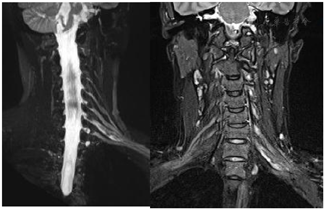

术前颈部MR平扫+增强(图1)与术前MRI-3D臂丛神经重建(图2)

颈部MR平扫+增强及臂丛神经MRI-3D重建显示左颈部占位考虑神经源性肿瘤可能性大。

对于臂丛神经鞘瘤,手术前明确诊断十分重要。由于缺乏典型的临床特征,该肿瘤的临床诊断较困难,即便是些专攻周围神经疾病的外科医生也常误诊为"肿大的淋巴结"。曾有学者等报道了2例癌症患者,在行PET-CT检查均发现在腋下或锁骨下区有高代谢的肿物,考虑为恶性肿瘤转移的淋巴结,然后行手术切除时术中才发现其来源于臂丛神经,从而考虑为臂丛神经鞘瘤[3]。除了常规的病史及体格检查外,MRI检查被认为是显示臂丛神经及其疾病较好的影像学检查方法[4]。术前常规MRI检查能清楚地显示肿瘤的部位、大小及其与臂丛神经的关系。T1加权像上肿物信号等于或略低于肌肉信号,T2加权像上肿物信号较高,可接近脑脊液信号。其注射增强剂后表现为中等度强化,但强化多不均匀。另外更进一步,本案例在常规MRI基础上对臂丛神经进行3D重建定位,使得肿瘤与臂丛神经的关系清晰可见,对于手术中神经保护有极其重要的参考价值。